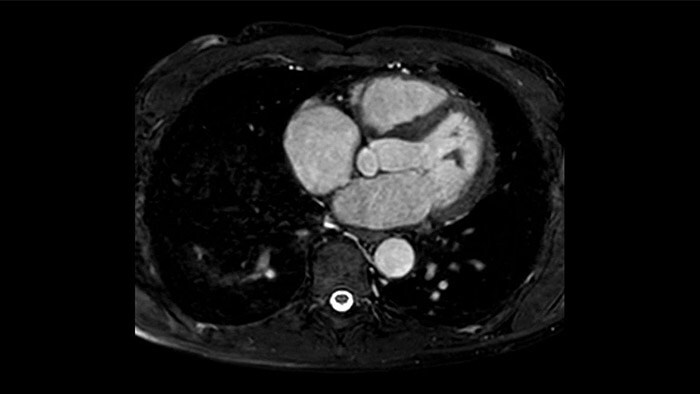

La diagnostica odierna spesso non è in grado di rilevare le disfunzioni cardiache fino a quando non si manifestano sintomi. MyoStrain valuta la deformazione del miocardio in 48 segmenti cardiaci e fornisce ai medici uno strumento diagnostico utile per identificare con anticipo la disfunzione funzionale prima che il cuore nel suo complesso sia compromesso.

La diagnostica tradizionale non offre la visibilità necessaria per vedere gli effetti di un trattamento cardiaco o individuare disfunzioni prima che si verifichino i sintomi. Combinando la sequenza di acquisizione MRI Fast-SENC di Philips con lo strumento di analisi MyoStrain di Myocardial Solutions, i lievi cambiamenti precoci nella funzione cardiaca possono essere misurati direttamente.

L'utilità diagnostica e prognostica della RM cardiaca è in continua crescita. È possibile valutare l'anatomia e la funzionalità cardiache utilizzando acquisizioni cine, ottenere informazioni sulla perfusione e vitalità del tessuto cardiaco, visualizzare potenziali edema con la sequenza Black Blood, accedere e persino quantificare la caratterizzazione dei tessuti con CardiacQuant.

IntelliSpace Portal MR CaaS5,6 Strain7 supporta nella diagnosi e nel monitoraggio dei pazienti fornendo parametri globali di strain, quali strain longitudinale globale (GLS), strain circonferenziale globale (GCS) e strain radiale globale (GRS), utilizzando immagini RM in asse corto e lungo e descrivendo inoltre la deformazione del miocardio, come il suo accorciamento, ispessimento e allungamento durante il ciclo cardiaco.